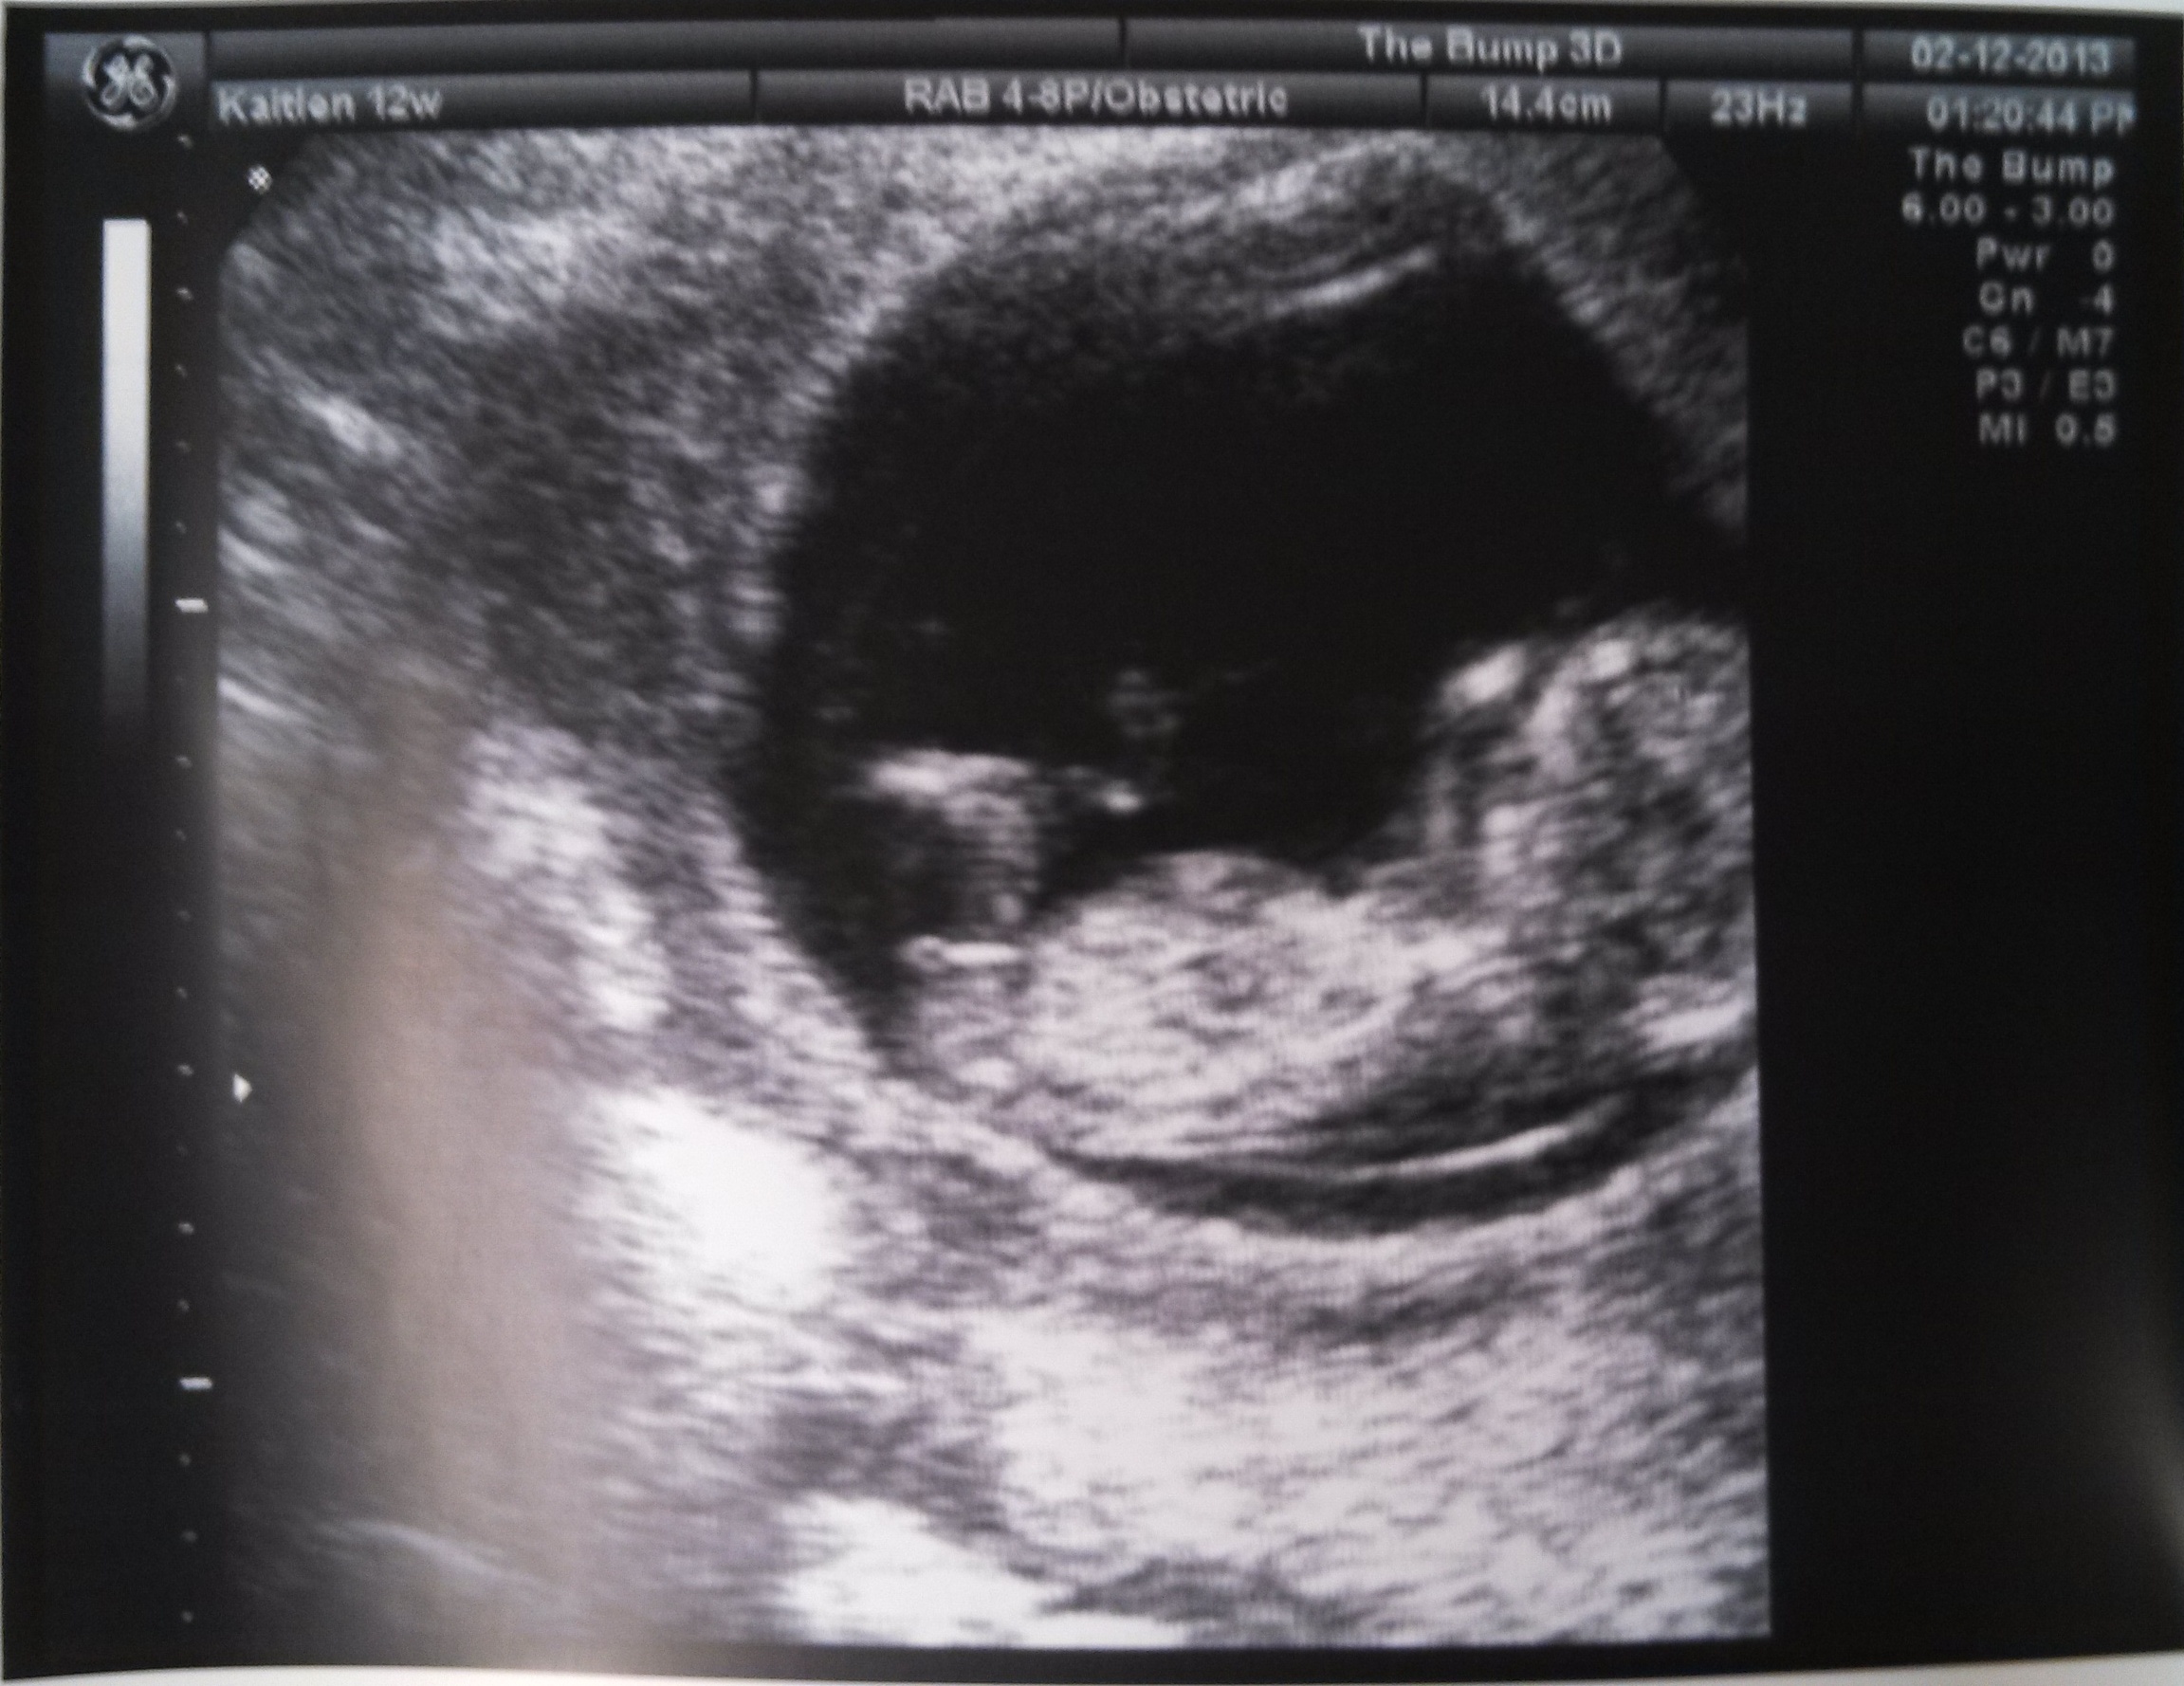

Hello! My daughter is 12 weeks and 2 days. She had an ultrasound at 11 weeks 6 days. Here are three of the pics. What do you all think?